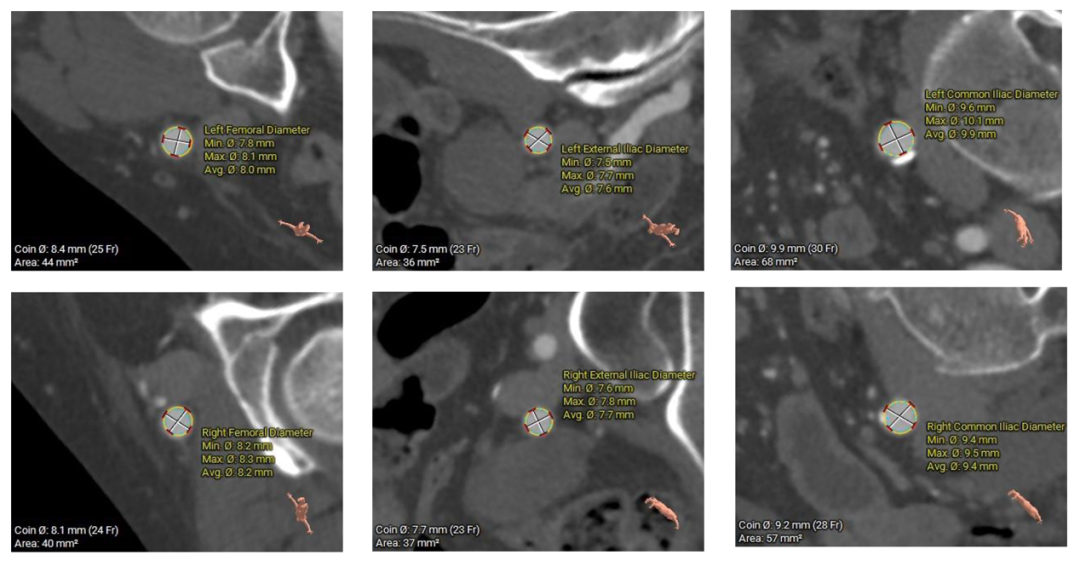

外周入路

Type-0型二叶瓣,中-重度钙化伴瓣叶增厚,左冠开口高度偏低,右冠开口高度可,左冠瓣叶长度略大于冠脉开口上缘与瓣叶附着缘距离,左室流出道整体呈直筒型,瓦氏窦,窦管交界,升主动脉内径可,左室腔内径可,心室壁增厚,主动脉瓣环与水平面夹角51度,非横位心,主动脉弓距、弓角可 -双侧入路血管走形良好,整体入路条件可

使用沛嘉20mm球囊预扩,预装沛嘉TaurusElite AV23瓣膜,释放高度瓣上0-2mm